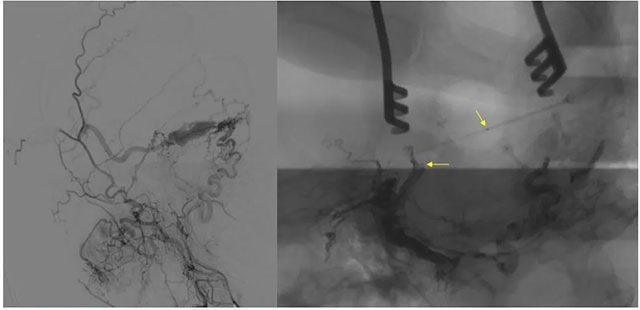

▲ 术前定位

8月23日,在复合手术室,在长海医院方亦斌教授指导下,张琪博士根据之前造影手术标记点确定平行左侧外耳道手术切口约 8cm,切开头皮各层至颅骨,剥离骨膜,牵开,以咬骨钳咬开一约 3cm 缺口,充分暴露横窦。

▲ 造影确认位置后,穿刺左侧横窦,置入 Echelon10 微导管

▲ 再次造影确认位置后,填入 HELIX 6/20弹簧圈

经左侧股动脉以单弯造影管超选至左侧颈总动脉造影明确静脉穿刺点入路,予以穿刺针穿刺成功后造影明确在位,随后 Echelon 10微导管到位横窦,填入一枚弹簧圈做塞子,造影明确位置后,缓慢注入 Onxy18胶 5毫升,铸胶弥散良好,通过静脉逆向弥散至部分供血动脉内。复查造影,见瘘口完全被栓塞,引流静脉消失,手术成功。